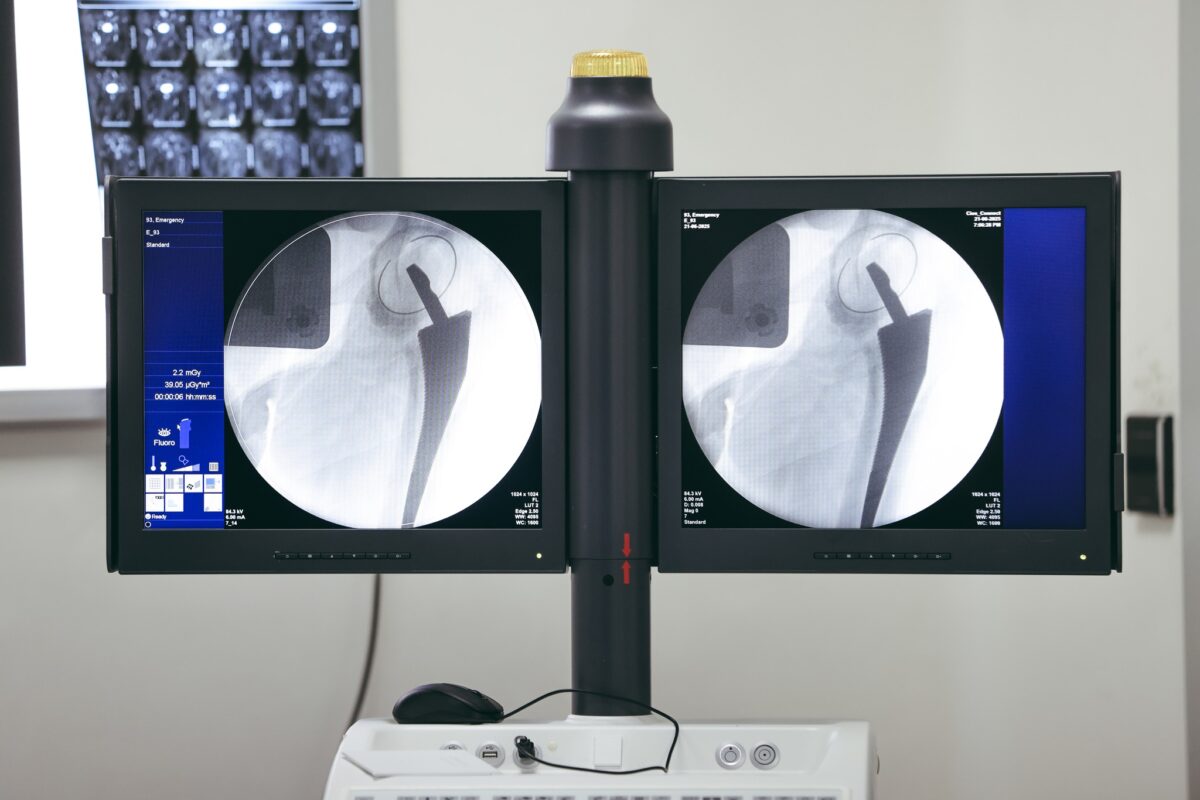

أُجريت عملية دقيقة ومعقدة لاستبدال مفصل الحوض بالكامل لسيدة تبلغ من العمر 54 عامًا، كانت تعاني منذ سنوات من آلام مزمنة وشديدة نتيجة تشوّه خُلقي بعظمة الفخذ، ما أثّر بشكل كبير على قدرتها